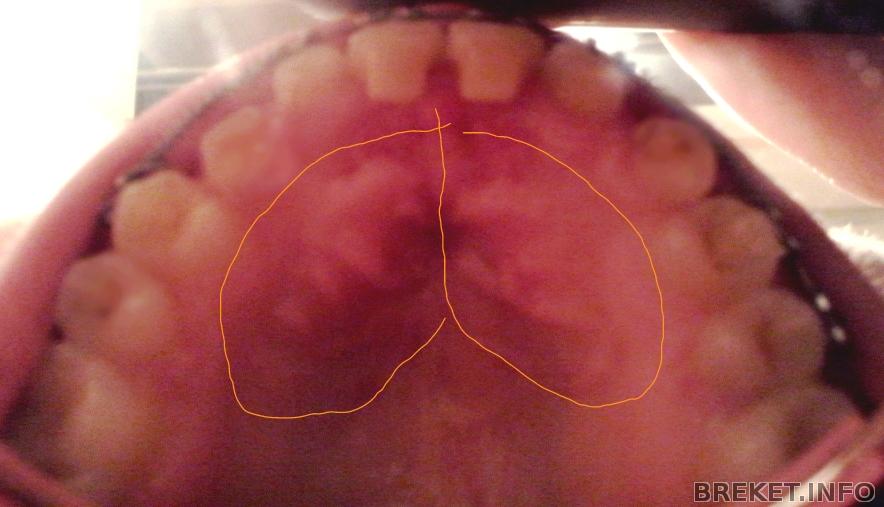

И вчера же я ходила на рентгеновский снимок "моих клыков " . Вот кстати и он . . .